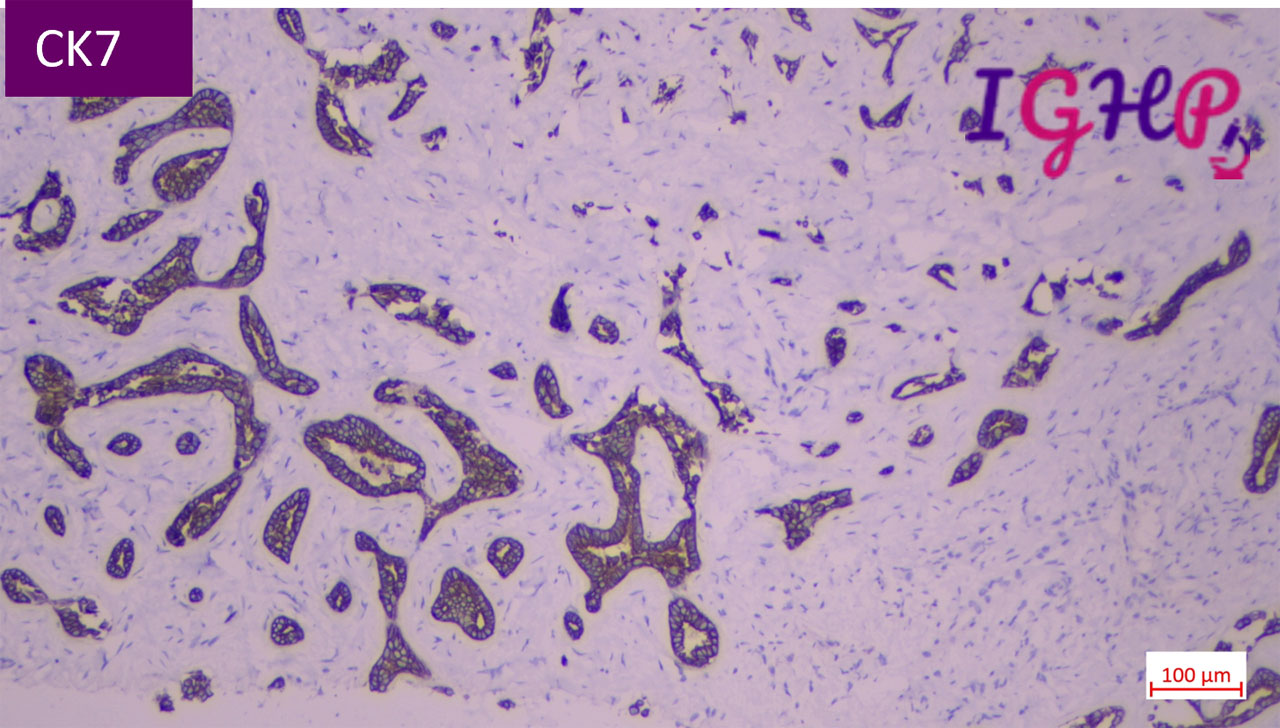

Immunohistochemistry Performed-

IHC performed for CK7, KI67 and P53